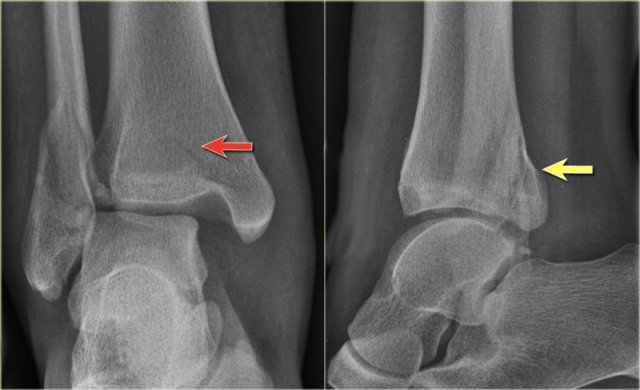

Weber B fracture Weber B fracture

The radiographs show a typical Weber B fracture.

First study the images and then continue reading.

Do you see what stage this is?

This is a Weber B stage 4 injury.

Notice that all 4 stages are visible:

1. Rupture of the anterior syndesmosis - seen as widening of the space between the distal tibia and fibula (lateral clear space).

2. Oblique fibula fracture at the level of the syndesmosis - i.e. Weber B fracture.

3. Tertius fracture - seen on AP view (red arrow) and on lateral view (yellow arrow).

4. Rupture of the medial collateral ligaments - seen as widening of the space between the medial malleolus and the talus (medial clear space)